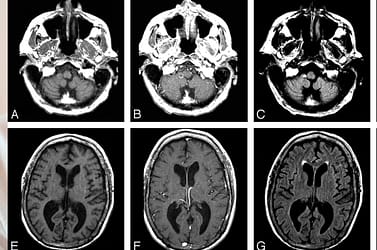

Natürliche Behandlung von Gehirnmelanomen im Stadium 4 mit Metastasen